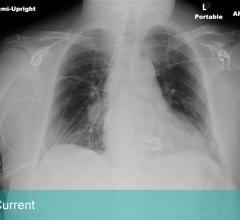

Digital X-ray replaces the use of film or computed radiography (CR) plates with a direct digital transfer of X-ray images into the PACS. Digital radiography (DR) is the direct conversion of transmitted X-ray photons into a digital image using an array of solid-state detectors such as amorphous selenium or silicon, with computer processing and display of the image. DR X-ray systems are used for both fixed base room installations and mobile DR, or portable DR, systems that are wheeled between room for imaging exams. Here is a link to the portable DR systems product comparison chart. Here is a link to the DR Systems chart that includes fixed room based systems and retrofit systems to replace film and CR.

The COVID-19 pandemic brought about an uptick in the demand for imaging services. A fast, accessible method was critical ...

March 29, 2021 — X-rays, first used clinically in the late 1890s, could be a leading-edge diagnostic tool for COVID-19 ...